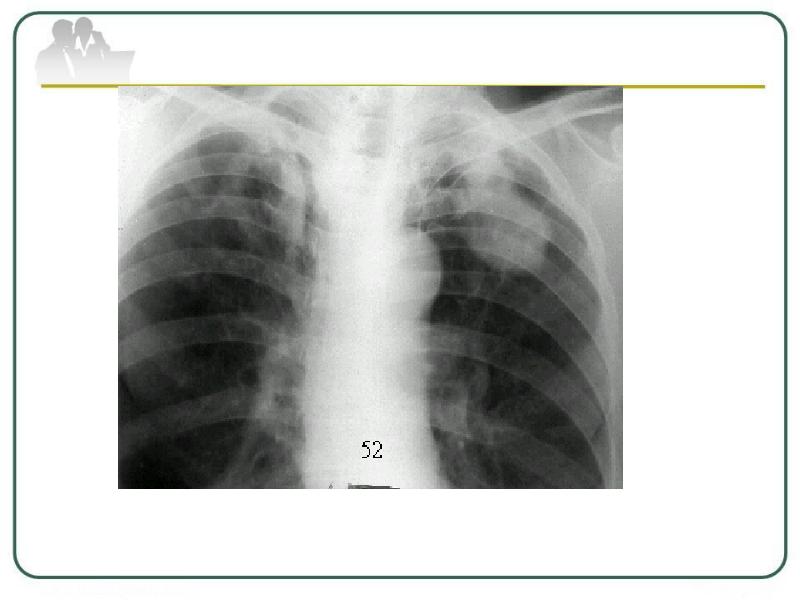

Очаговый и инфильтративный туберкулез презентация - 94 фото